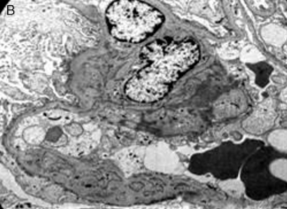

3. Microscopio electrónico

1. Borramiento difuso de los podocitos y puede haber desprendimiento focal de células epiteliales

1. Imagen de un área glomerular con fusión pedicular, incremento de matriz mesangial y depósitos electrodensos